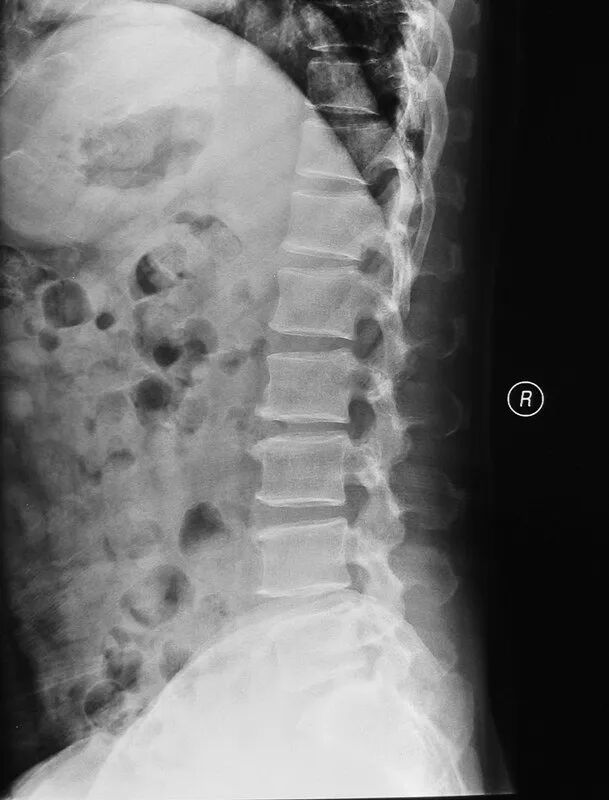

X线

X线可了解到腰椎的生理曲度、椎间隙改变、是否有骨质增生、关节错位等。